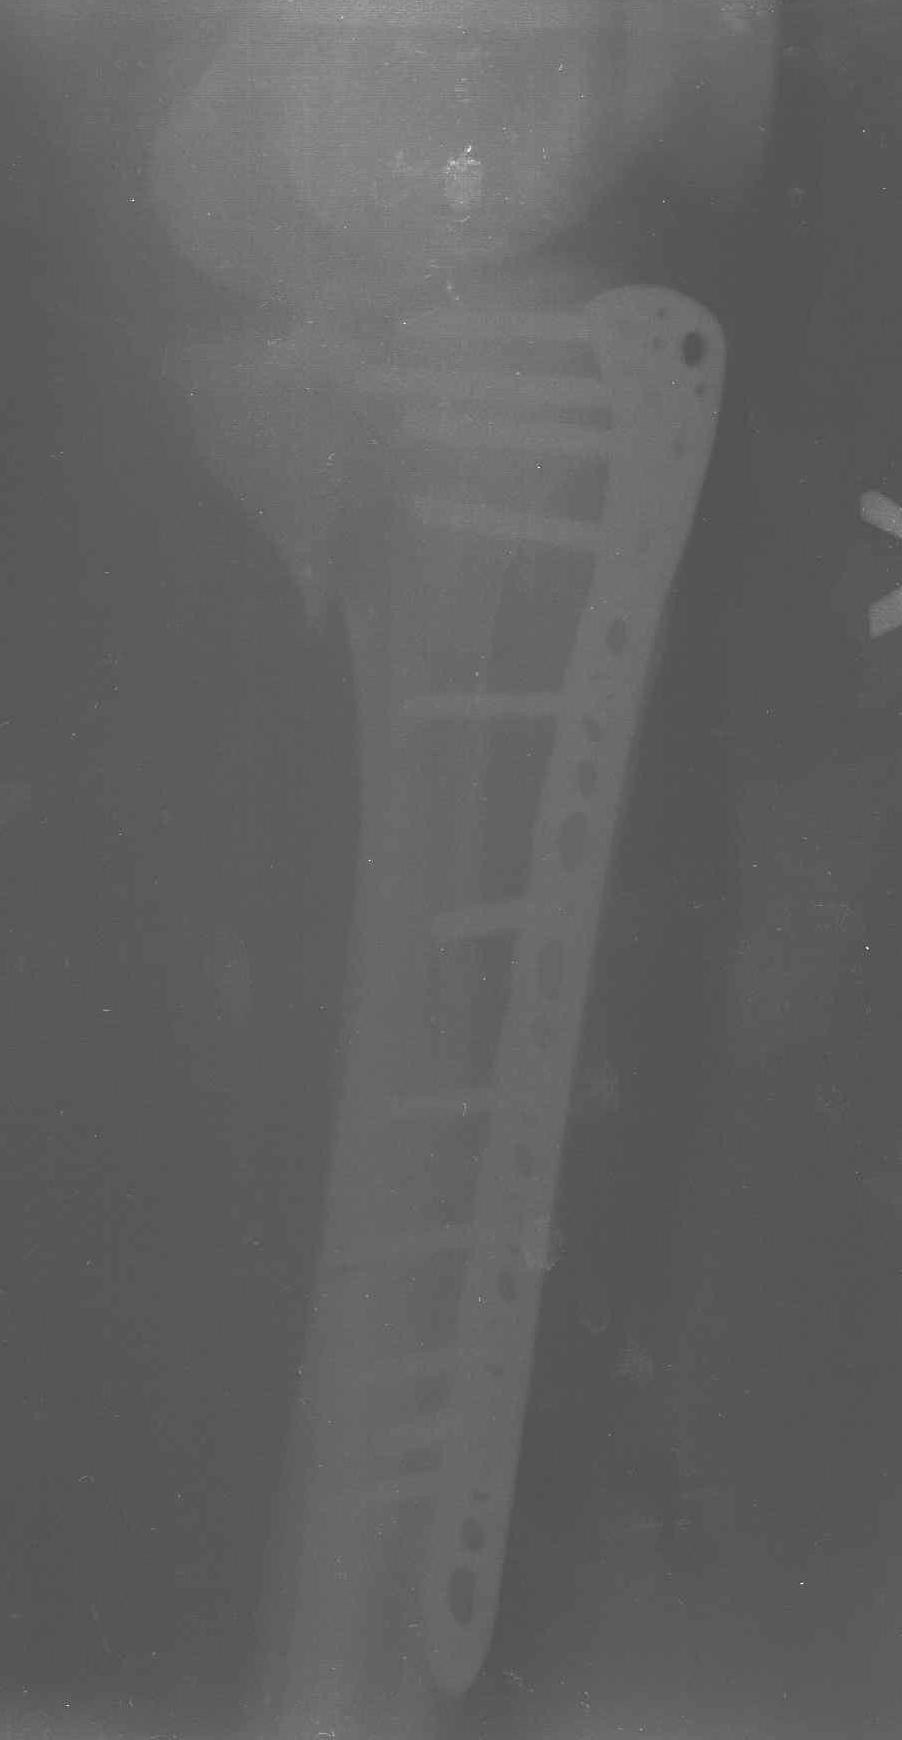

Уважаемые коллеги! В прошлую пятницу больной прооперирован - как и планировалось мыщелковая LCP от ChM. Малоинвазивно не получилось - один большой доступ :(. (но с минимальным скелетированием б/б кости). Наружный мыщелок собрали, но по контролю видно, что задне-медиальный отдел метаэпифиза смещен. Фиксировать не стали (?). 4-е сутки после операции - по м/тканям без проблем. Дополнительная иммобилизация синтетическим тутором.

Интересно услышать ваши мнения, анализ ошибок...

P. S. перелом диафиза на контроле не совсем захвачен, но проблем там нет. Приношу извинения за низкое качество Р-грамм - выполнены на сканере (фотоаппарат не работает :)) .

Трудно поверить, что разрекламированная Ортопедическая школа Восточной Украины позволяет такие странные снимки? На прямом снимке сохранен общий контур плато, но не известна судьба импрессии суставной поверхности. На полубоковой?, оставлен без репозиции задне-медиальный отдел, и навряд ли после такой фиксации можно удовлетвориться результатом.

Такая ситуация характерна для многих, когда принимается ошибочное решение, т.е пытаются фиксировать одним имплантом переломы двух мыщелков. Латеральная пластина приемлема только для тех случаев, когда сохраняется интактным медиальный диафизарный кортекс и отсутствует фрагментация на верхушке медиального перелома.

Представленные снимки не информативны, нужны отдельные качественные снимки коленного сустава и голени без ротации.